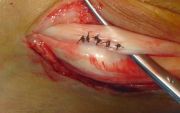

1. Ηallux valgus of the right foot in a 28-year-old female.

Treatment: Scarf osteotomy of the first metatarsal

I. Anteroposterior x-ray foot during procedure shows the scarf osteotomy with two screws II. This image shows the foot in a standing position one year down the line from the procedure. The young lady is very happy.